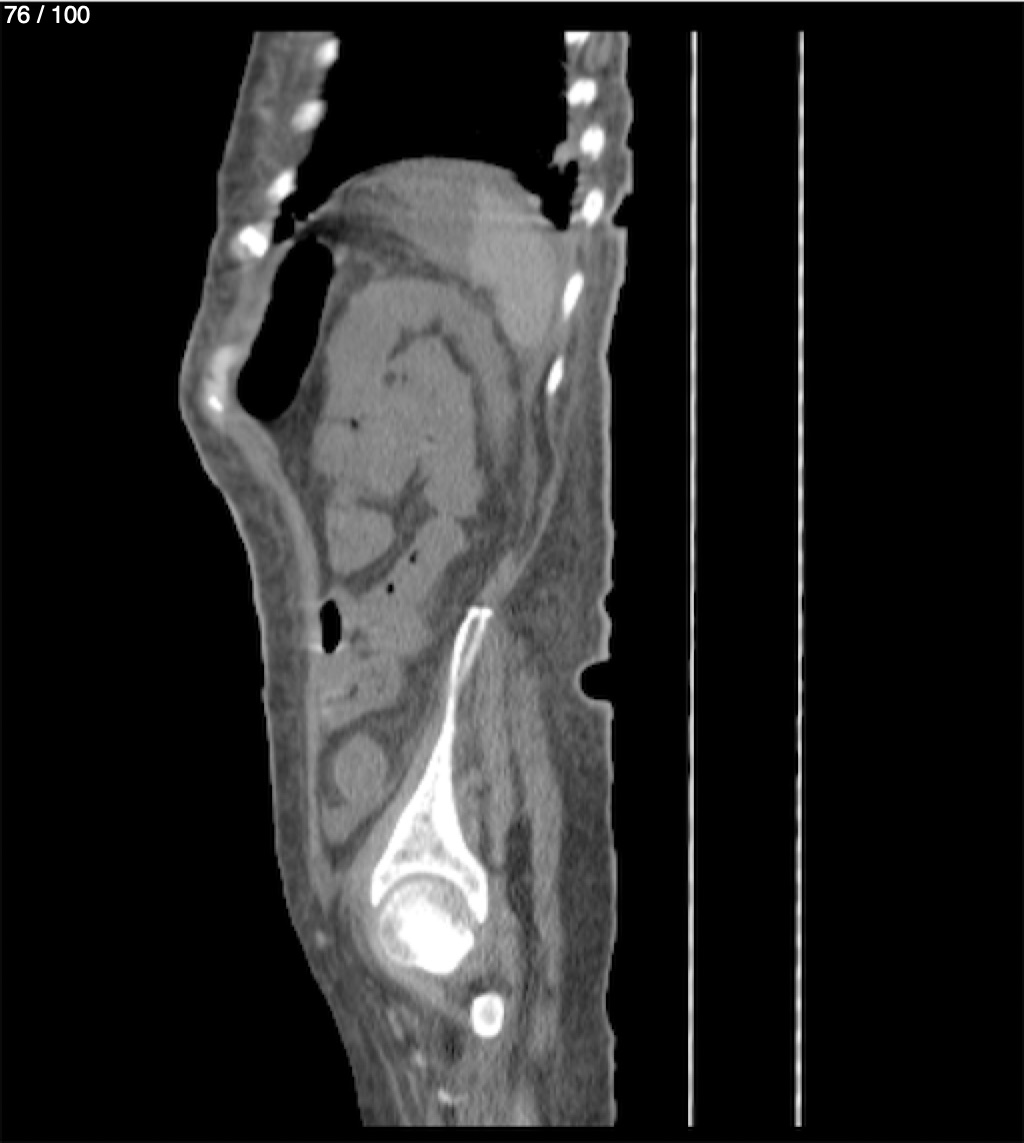

Hilda Geronimo Mendez 60A - T.C Abdomen Simple